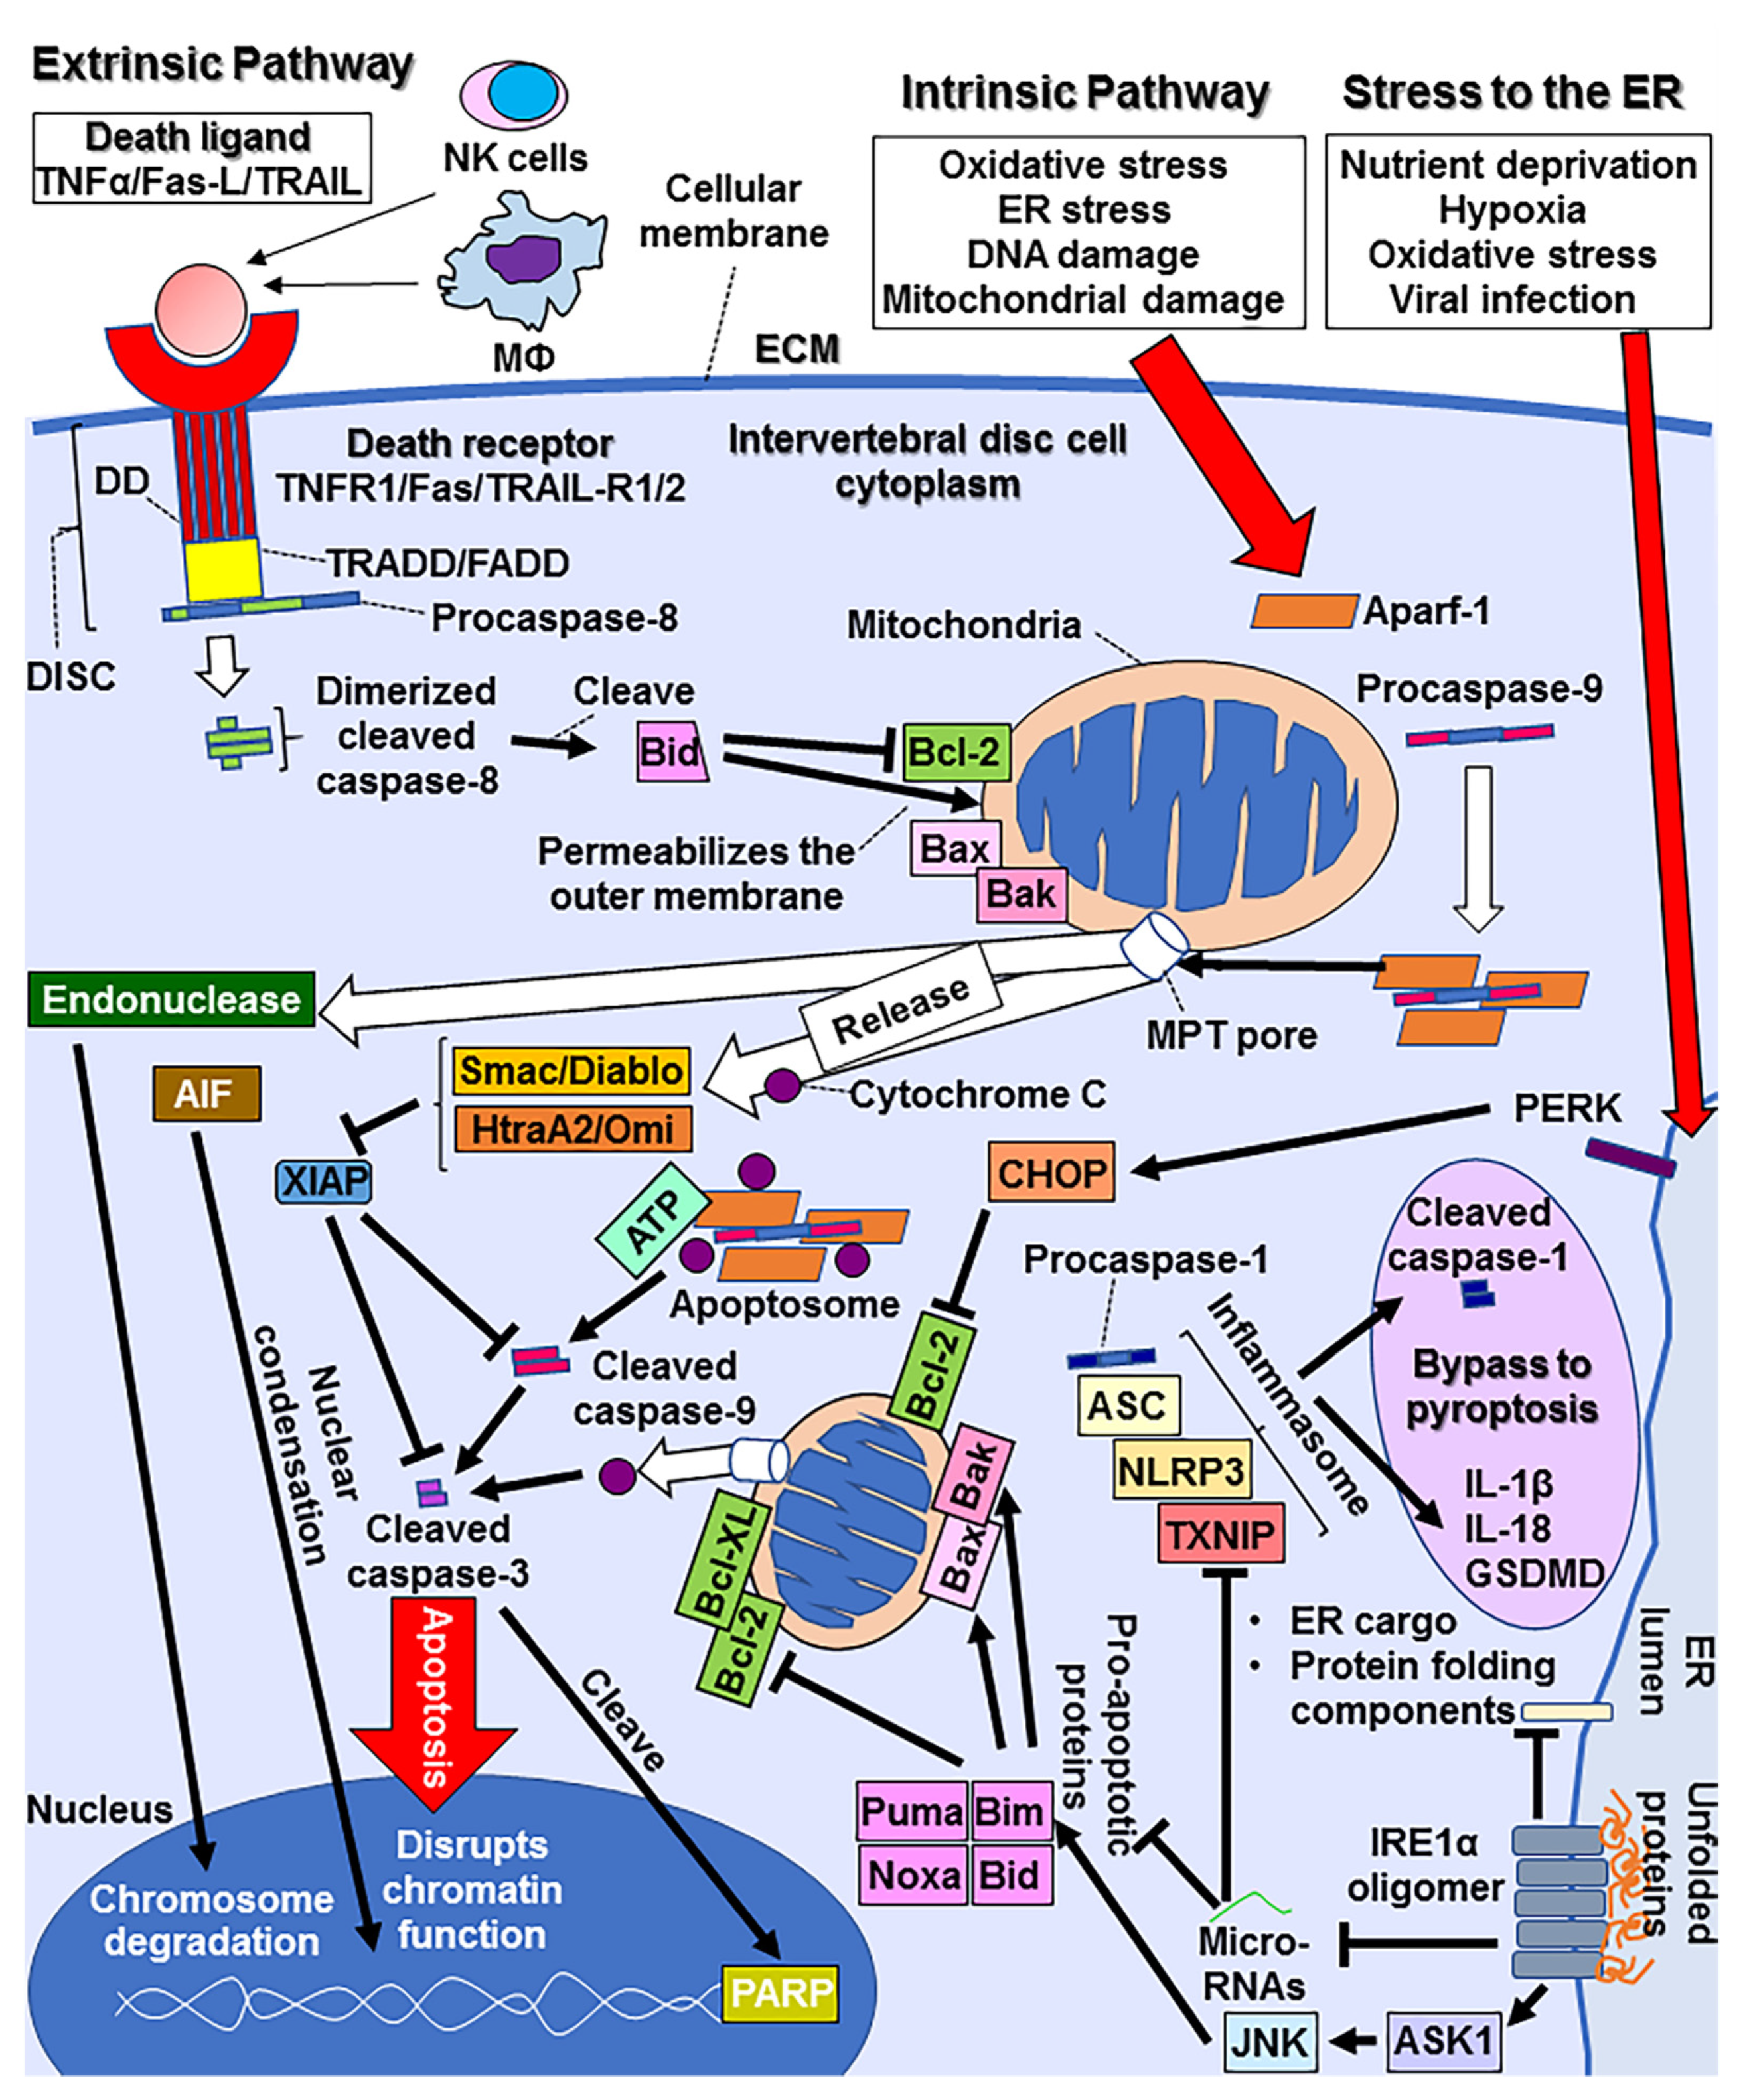

61UWIqrokYL.jpg。Autologous fibroblasts induce fibrosis of the nucleus。Intervertebral Disk Herniation。令和6年産 新米コシヒカリ 5.キロ。

。Frontiers | Intervertebral disc degeneration—Current。[A01151548]動画で見る音声障害 Ver.1 [DVD] (1) 日本音声言語医学会。[A01371176]リウマチ生活指導 (リウマチのリハビリテ-ション (第1集)) 椎野 泰明。[A01206585]泌尿器ケア 13年9月号 18ー9―泌尿器科領域のケア専門誌 泌尿器科術前・術後のケアマニュアル [単行本]。[A01438740]膠原病診療ノート―症例と文献の分析に基づく実戦的マニュアル 三森 明夫。Doctor Stories Dr.コトー診療所のモデル。[A11076679]消化器内視鏡 第24巻11号 20 これは役立つ十二指腸病変アトラス (消化器内視鏡2012年11月号) 消化器内視鏡編集委員会。[A01214448]救急医学 2012年 01月号 [雑誌]。[A11849401]非浸潤性乳管癌のすべて [単行本] 秋山 太。[A12284976]スラッター 小動物の外科手術(全2巻)